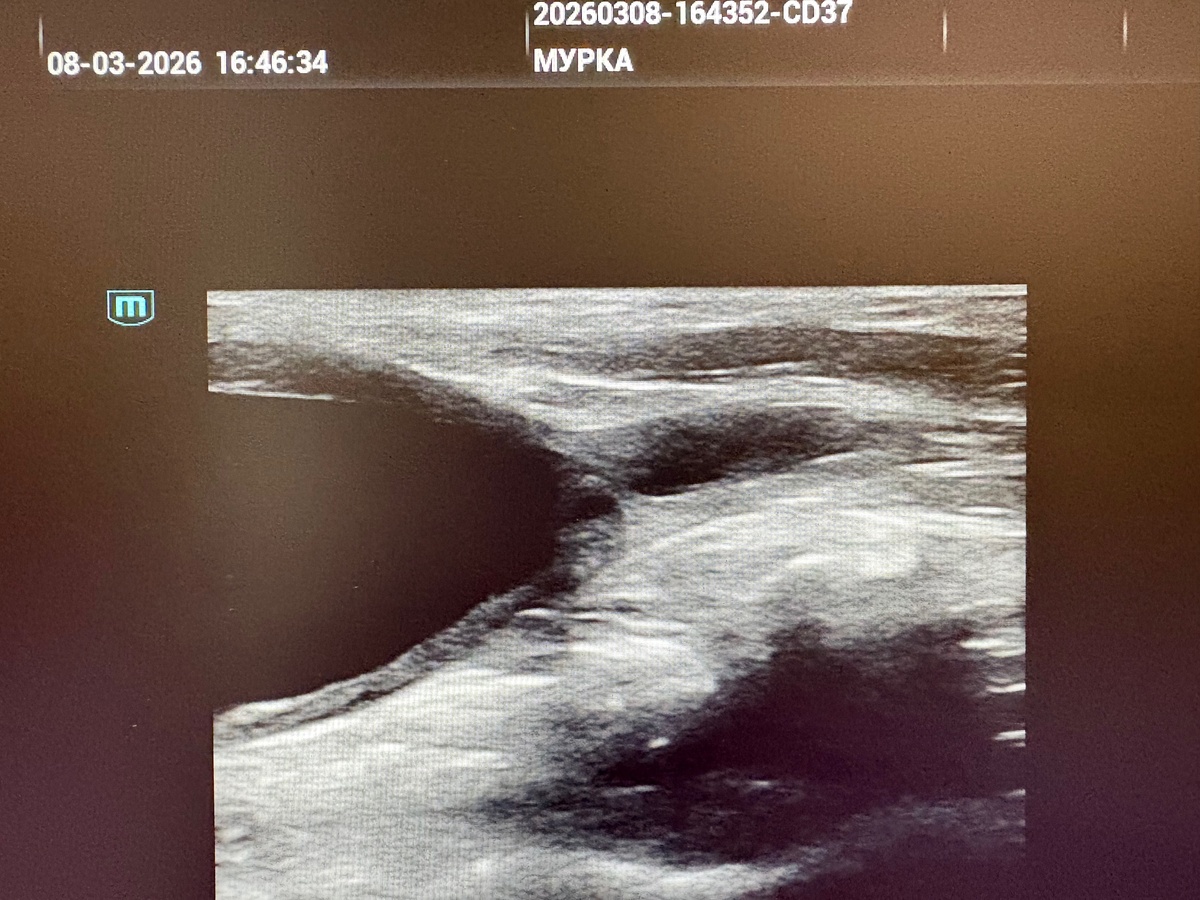

МУРКЕ нужна операция!

Наша чудесная плюшевая Мурка снова в беде. В далеком 2019 году мы впервые прооперировали её в Москве vk.ru/wall-17702885_51380 и тогда фото с её операции и историю болезни врачи растащили для статей - столь интересный и сложный оказался случай. Наш врач называет это непонятными словами «дивертикул мочевого пузыря», «урахус», «гиперплазия слизистой на фоне хронического ИЦК»…сложно… но ясно одно - ВОПРОС ЖИЗНИ И СМЕРТИ!

УЗИ: выход из мочевого пузыря в уретру зарос слизистой пленкой, пока пробили катетером, но это временная мера - надо оперировать. Почему Москва? Там есть нужное оборудование (эндоскоп) и умеющий обращаться с ним хирург. Да, дороже, но третью полостную операцию с разрезанием мочевого пузыря надо постараться избежать любыми путями.